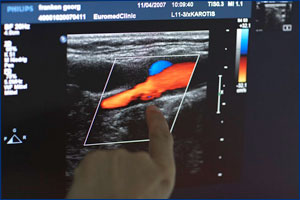

При наличии отложений в сосудах, по итогам дальнейших исследований (цветовой ультразвук, исследование сосудов с использованием контрастного вещества) мы можем оценить масштаб заболевания сосудов и начать соответствующую терапию, например, при помощи катетерной техники. К. м. н. Зузаннэ Шелль специализируется на ультразвуковой диагностике. Дополнительные пробы крови (определение сахара в крови, холестерина, мочевой кислоты и пр.) позволяют определить соответствующие показатели, на основании которых мы можем посоветовать Вам наиболее оптимальное медикаментозное лечение.

В случае венозных заболеваний врач уже на основе обследования организма может выявить у обследуемого пациента первые признаки слабой соединительной ткани и предрасположенности к тромбозам, а на основании целенаправленной диагностики при помощи функциональных тестов, цветового доплеровского исследования и рентгенологического обследования можно исследовать венозную функцию и предложить обследованному пациенту индивидуальную терапию.